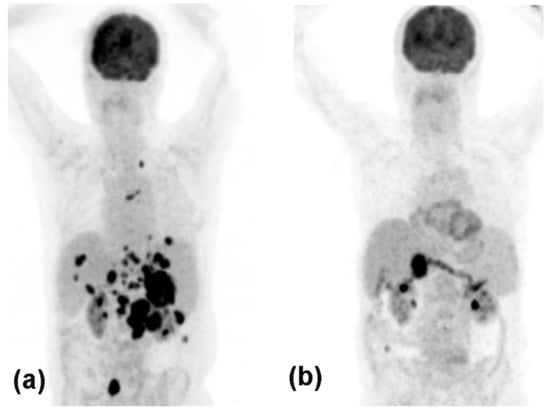

- Hodi, F.S.; Lawrence, D.; Lezcano, C.; Wu, X.; Zhou, J.; Sasada, T.; Zeng, W.; Giobbie-Hurder, A.; Atkins, M.B.; Ibrahim, N.; et al. Bevacizumab plus Ipilimumab in Patients with Metastatic Melanoma. Cancer Immunol. Res. 2014, 2, 632–642. [Google Scholar] [CrossRef] [PubMed]